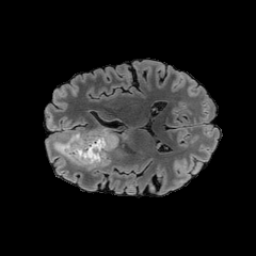

Tumour Information Preservation. For the brain tumor segmentation, we use a Swin UNETR model[28, 70], trained with random rotation, and intensity as data augmentation. On the test set with human ground-truth annotations (), the brain volumes generated from single slice input preserve the volume of the different tumour components (paired t-test, for all 3 classes). In Figure 4, we highlight the tumor profiles of the generated MRIs compared to the ground truth tumour profile. The real MRI Dice score in the test set is 85.15 while the generated MRIs from a single slice have a dice score of 83.09. This shows how the generated MRIs indeed preserve the tumor information and can act as an affordable and informative pseudo-MRI, before conducting an actual costly MRI examination in hospitals. More detailed results are provided in supplementary material.

Leveraging Context. Since we train on a predominantly cancerous brain dataset, one question that might arise is whether X-Diffusion generated MRIs preserve tumour information when the given inputs do not intersect with any tumour. We perform experiments varying the input slice index used to generate the 3D brain MRIs and measure the performance for input slices with no intersection with the tumour (not a single pixel with tumor label in the input slice). We also measure performance when only input slices are selected from tumor range. The Dice Scores of the random slices, no-tumour, and only-tumour are 83.09, 79.23, and 83.68 respectively. As can be seen here, the brain volumes generated from input slices with no tumour still preserve tumour information in reconstructed brain volumes despite a small drop in performance. This indicates that X-Diffusion is leveraging the context to preserve key information, such as tumor locations. This observation is consistent with how tumor segmentation models with global context [13] perform better than local-based U-Nets. More details are provided in supplementary material.

To see when and how X-Diffusion fails, we conducted an experiment on healthy brains (no tumour) using IXI dataset, by running an X-diffusion trained on BRATS brain tumor dataset. Our X-Diffusion achieved a PSNR of 35.86 dB on the IXI dataset despite being trained on the BRATS dataset. We then ran the tumour segmenter on the set of 582 healthy scans and corresponding generated MRIs. The segmenter predicted tumours in 9.9% of the real healthy brains and in 11.3% of the generated brain MRIs. Some of these tumor hallucination examples fron X-Diffusion generation are shown in Figure 10.

On the test set with human ground-truth annotations (), the brain volumes generated from single slice input preserve the volume of the different tumour components (paired t-test, for all 3 classes) (see Table I). The real MRI Dice scores are put for reference to our generated MRIs. X-Diffusion outperforms baselines TPDM [39] and ScoreMRI [19] in tumour preservation (see Table I and Figure III). We ran experiments comparing the tumour segmentation Dice Score varying X-Diffusion configurations. The multi-slice input X-Diffusion achieves marginally better Dice Score than the single slice input model (83.47 83.09). We also ran experiments with slice input used for volume reconstruction intersecting or not with tumour. We observe on average a drop of 6% Dice Score (see Table I). Further away from the tumour the input slice for volume reconstruction is selected, we observe a linear decrease in tumour segmentation Dice Score with lowest value of 77.21 Dice Score (see Figure VI).

This shows how the generated MRIs indeed preserve the tumour information and can act as an affordable and informative pseudo-MRI, before conducting an actual costly MRI examination in hospitals. Given that our model has been trained on brain scans all with tumours, we expect to see hallucinations of tumours in healthy scans. We report two cases of failure of our model in Figure VII. Hallucinations of tumours on healthy samples represent 2% of the test set.